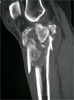

Pre

Op

Xrays